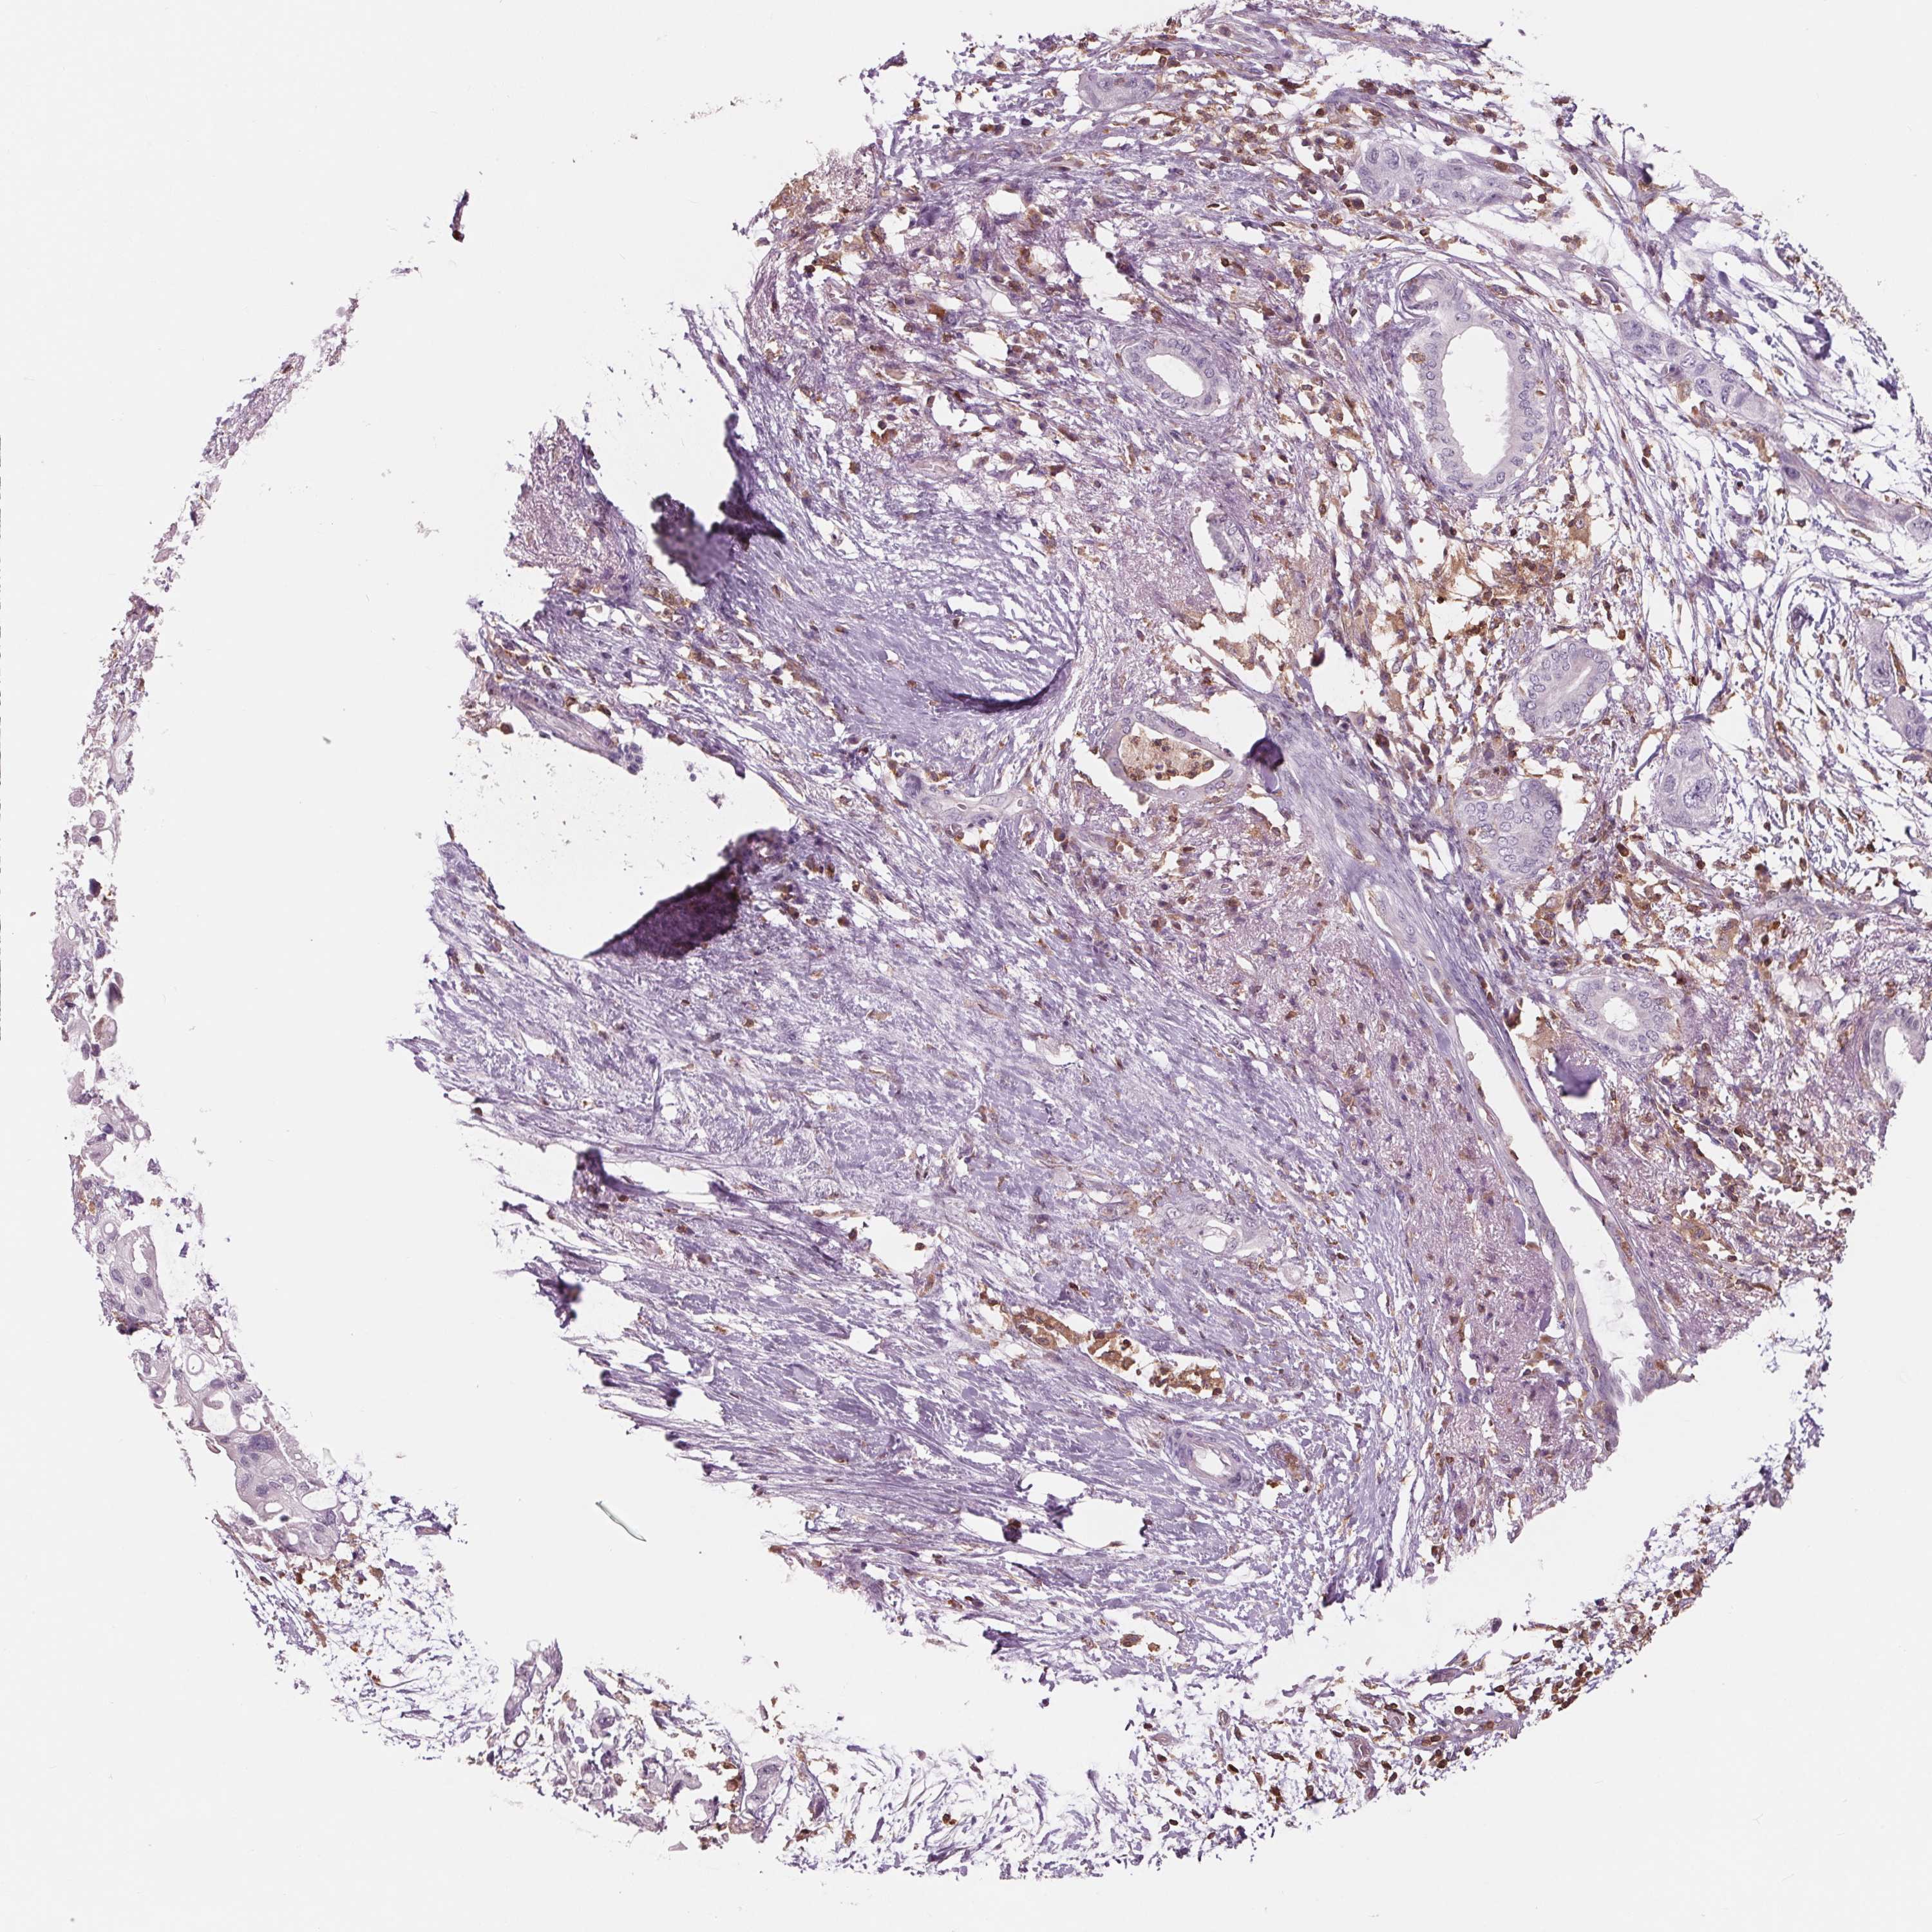

PANCREATIC CANCER - Protein expressioni

A mouse-over function shows sample information and annotation data. Click on an image to view it in a full screen mode. Samples can be filtered based on level of antibody staining by selecting one or several of the following categories: high, medium, low and not detected. The assay and annotation is described here.

Note that samples used for immunohistochemistry by the Human Protein Atlas do not correspond to samples in the TCGA dataset.

Antibody stainingi

Antibody staining in the annotated cell types in the current human tissue is reported as not detected, low, medium, or high, based on conventional immunohistochemistry profiling in selected tissues. This score is based on the combination of the staining intensity and fraction of stained cells.

Each image is clickable and will lead to virtual microscopy that enables deeper exploration of all samples and also displays staining intensity scores, fraction scores and subcellular localization as well as patient and tissue information for each sample.

Antibody HPA035346

Antibody HPA061395

Staining

High

Medium

Low

Not detected

Intensity

Strong

Moderate

Weak

Negative

Quantity

>75%

75%-25%

<25%

None

Location

Nuclear

Cytoplasmic/membranous

Cytoplasmic/membranous,nuclear

Adenocarcinoma, NOS